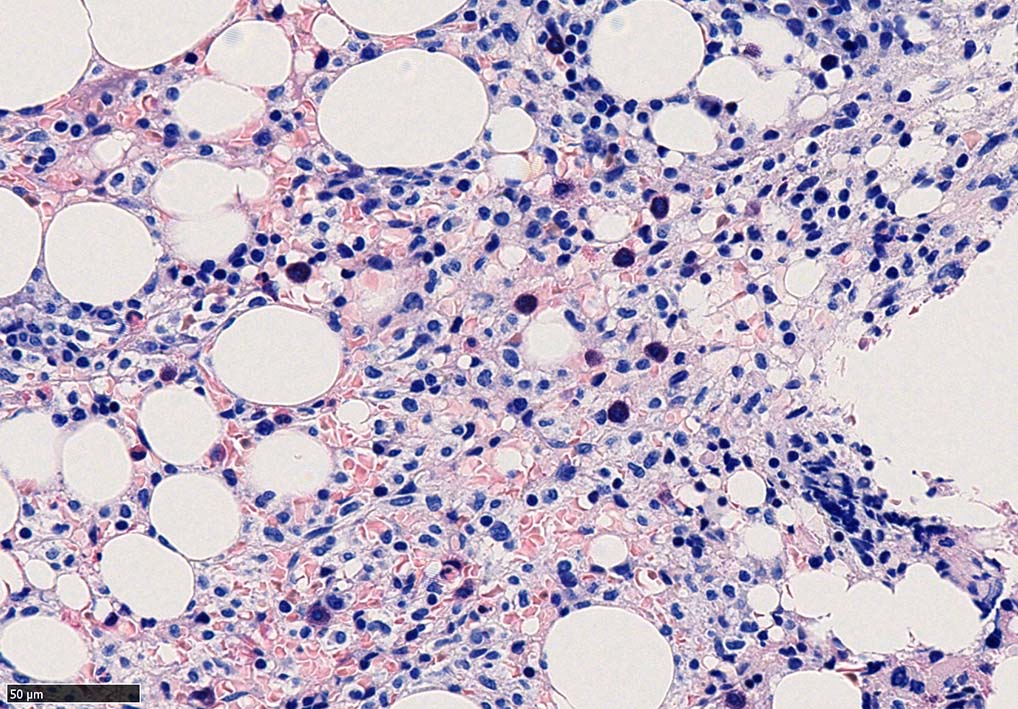

bone marrow trephine biopsy: dry tapのため骨髄生検が行われる. cellularityは40-80%とhypercellular marrow. 流れのある細胞配列は線維化を疑わせる.

ASD-G 低倍率所見では赤芽球血島は幼若赤芽球の集簇巣が散在する, 顆粒球系細胞(ASDに赤く染色される)は減少,granulopoietic hypoplasiaを呈する.疎な集簇を示すmast cellsの増加がある.

ASD-G陰性の細胞がびまん性に増加しているように見える.

ASD-Giemsa陰性の細胞がシート状に増殖する. 核はクロマチン濃染, 核小体は不明瞭.類円形, 卵円形, くびれを持つ多稜形核, 長円形いびつで屈曲した核, など多彩. 細胞質は淡清色調, 広く淡明. 赤芽球血島は幼若赤芽球のみで形成される異形成像を示す. やや離れて成熟赤芽球が疎な集簇を示す.

Ag染色では, 疎な弾性線維が増生し,増殖細胞を小胞巣状に分画するいわゆる「lymphomatoid pattern」を呈する. 本例では, Mgkに異形成所見がある.